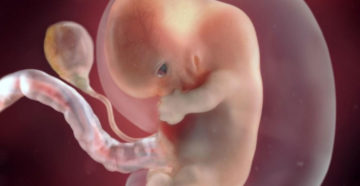

8 неделя беременности. Плод 8 недель Восьмую неделю беременности еще также называют шестой эмбриональной неделей….

8 неделя беременности Наверняка вы уже думали над именем ребенка и не раз гадали, мальчик…

8 неделя беременности: что происходит с малышом и мамой, ощущения, развитие плода Каждая неделя беременности…